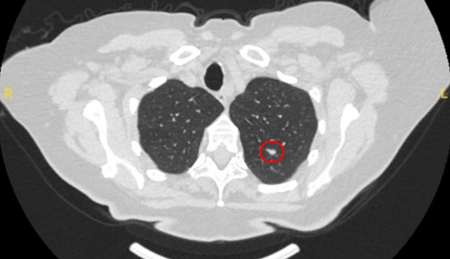

Nódulos benignos tendem a apresentar bordas bem definidas, enquanto nódulos malignos tendem a ser irregulares ou alongados. No entanto, muitas vezes, ocorre um grau de sobreposição e, considerada isoladamente, essa característica não pode ser usada com segurança como fator discriminador.[Figure caption and citation for the preceding image starts]: Tomografia computadorizada (TC) mostrando um pequeno nódulo no lobo superior esquerdo com margens lisas, posteriormente considerado uma metástase colorretal solitária na ressecçãoDo acervo de Dr. George Tsaknis, MD, PhD, FRCP (Londres), MRQA, MAcadMEd, PGCert; usado com permissão [Citation ends].